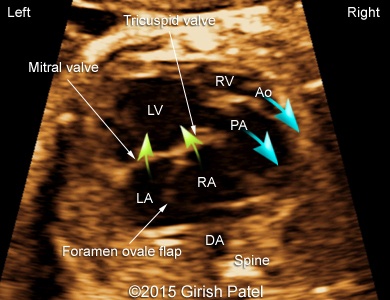

Following images and videos show a case of double inlet left ventricle with transposition of the great arteries that was seen at 26 and 36 weeks of otherwise non-complicated pregnancy.

Images 1, 2, 3, and 4: 2D images showing transverse scan of the heart with double inlet left ventricle and transposition of the great arteries. Following structures can be seen: dominant enlarged left ventricle (LV); diminutive right ventricle (RV) connected to the left ventricle via small bulboventricular foramen; both, left atrium (LA), and right atrium (RA) open to the left ventricle via separate tricuspid and mitral valves; foramen ovale flap can be seen within the left atrium; enlarged pulmonary artery (PA) arises from the left ventricle; small part of the aorta (Ao) arising from the diminutive right ventricle can be also seen.

Images 8, 9, 10: 2D gray scale and color Doppler images showing the heart with double inlet left ventricle and transposition of the great arteries - the images 8 and 9 show mitral and tricuspid valves opened to the left ventricle. The image 10 shows branching of the pulmonary artery (RPA, LPA), arising from the dominant left ventricle.

Videos 1-7: Gray scale and color Doppler videos showing video-loops of the heart with double inlet left ventricle and transposition of the great arteries. Following structures can be seen: dominant enlarged left ventricle, diminutive right ventricle connected to the left ventricle via small bulboventricular foramen; both, left atrium and right atrium are opening to the left ventricle via separate tricuspid and mitral valves; foramen ovale flap can be seen within the left atrium; enlarged pulmonary artery arises from the left ventricle in parallel arrangement with a smaller aorta arising from the diminutive right ventricle.